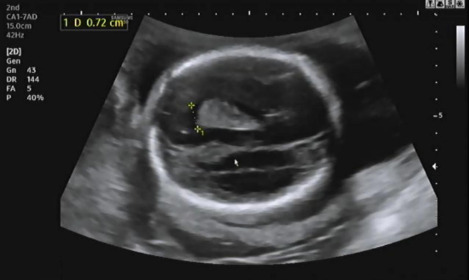

그다음 태아의 머리 둘레를 측정하고 21주 차에 맞게 뇌가 주수에 알맞게 발달하였는지, 물혹 등의 여부나 기형이 있는지 확인을 한다.